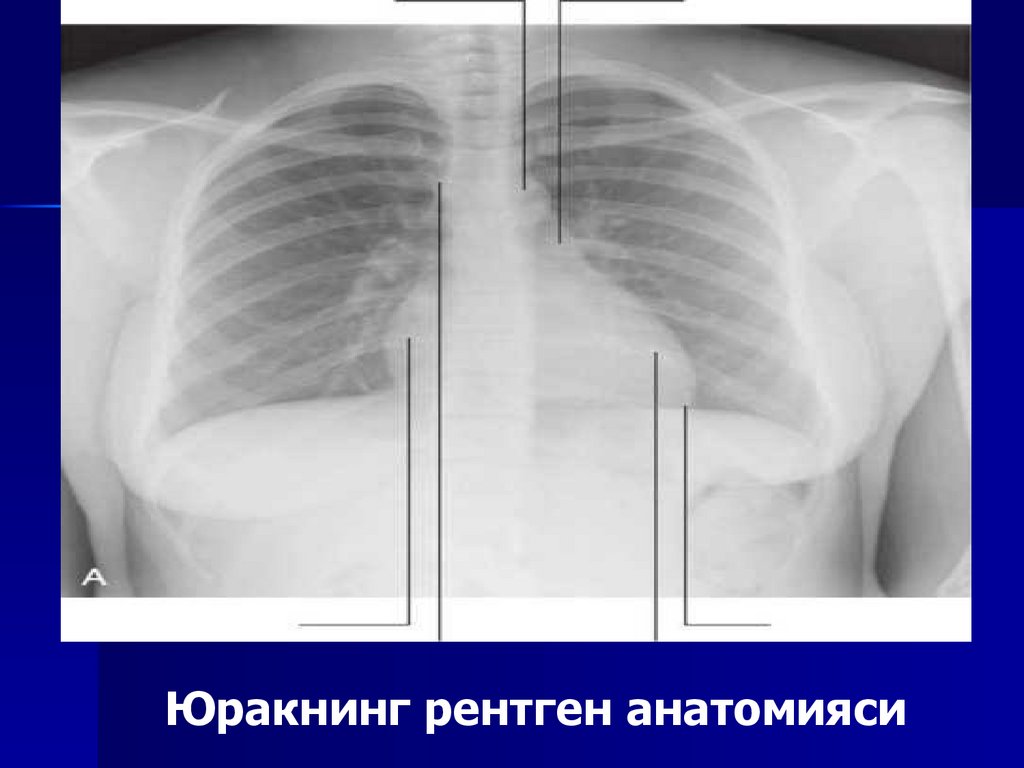

21. Юракни текшириш усуллари

Юрак бўшлиғи ва унинг йирик қон томирлари

уни ўраган ўпка тўқимаси соясида аниқ

гомоген соя беради. Юракнинг ўзини сояси

билан унинг йирик қон томирлари сояси

ўртасидаги чегара юрак-томир силуэтининг

энг торайган қисмига тўғри келиб, юрак бели

деб аталади. Юрак жойлашишининг 3та

асосий: қия, кўндаланг ва вертикал шакллари

учрайди

Юракнинг рентген анатомияси